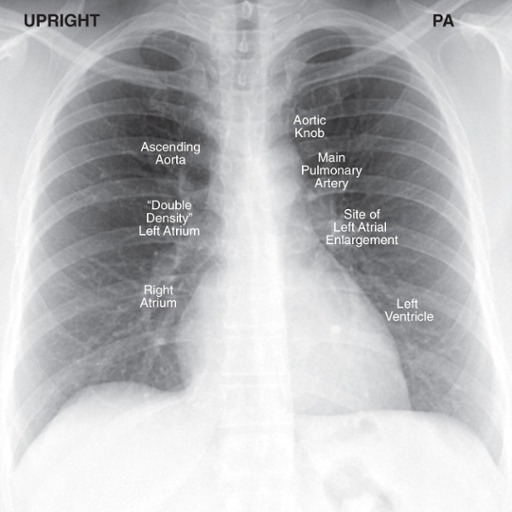

Cardiac Contours

Since we are looking at shadows (knowing the heart is soft tissue density), the silhouette of the heart demonstrates certain contours

Aorta – knob on frontal view

PA – vascular so visible, unlike bronchus; left main sits higher than right

Right and left atria – right atria makes up right heart border; left atria will enlarge superior portion of left heart border

LV – posterior structure; more prominent filling retrocardiac space on lateral

Descending aorta disappears because it is buried in mediastinal soft tissue densities